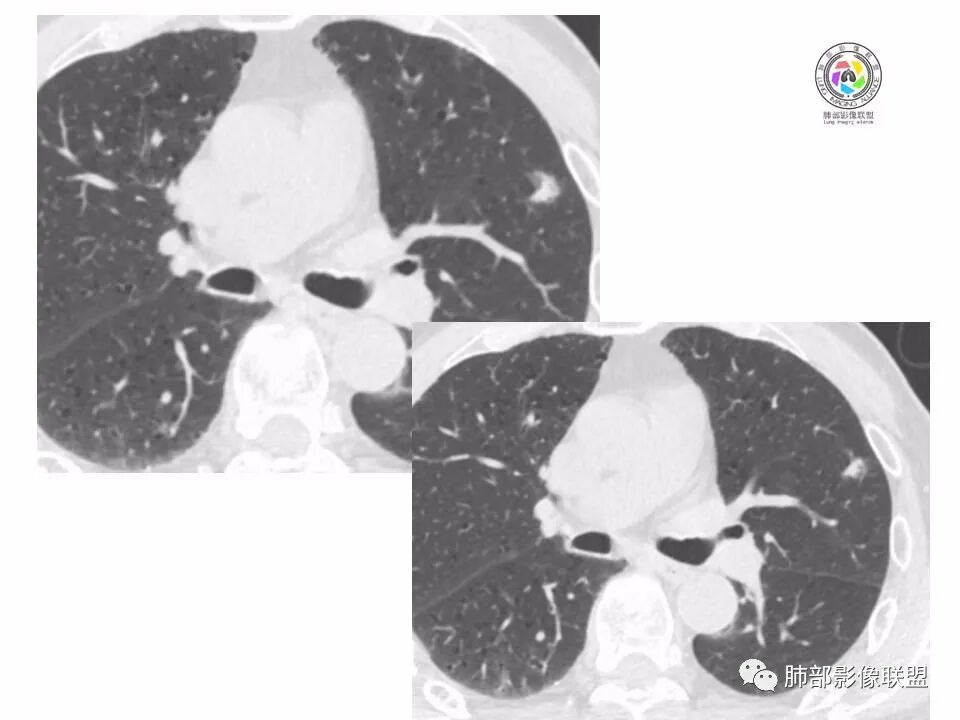

左肺上叶小结节,边缘毛糙,血管集束,支气管截断,强化较明显,但U型凹陷,部分边缘平直,总体感觉恶性大于良性,首选腺癌,鉴别炎性肉芽肿。

左上肺结节,月牙征,边缘纠集有收缩力,小空泡,血管增粗进入,纵隔淋巴结增大,考虑恶性,隐球菌待排。

老年男性,左上肺结节,边缘毛糙,临近血管进入增粗,内部隐约可见小空泡或远端扩张支气管,血管集束并伴月牙铲,有个横断界面看似像脐凹征,常规考虑腺癌,鉴别隐球。

结节,分叶,边缘毛糙,小空泡,血管集束并伴月牙铲,有强化,老年男性,考虑腺癌,建议复查除外结核。

左肺上叶混合密度结节,边缘见边缘清楚磨玻璃,分叶,U型凹陷,首先考虑腺癌。

左肺上叶结节影,边缘可见分叶,血管集束及月牙铲征,病灶内见小空泡影,考虑腺癌可能。

结节密度不均匀,混合磨玻璃结节,大部分实性部分,边缘清,月牙铲征,肿瘤微血管征,考虑肺癌。

老年男性,体检发现左肺上叶结节,周围浅分叶伴磨玻璃影,有血管相连,U型凹陷,纵隔见肿大淋巴结,考虑为恶性,腺癌可能。

左肺形态不规则结节,边缘收缩,毛刺,有月牙铲,纵隔窗比肺窗小,不密实,近段血管与病灶相连,强化不明显,老年男性,综合考虑,恶性,腺癌,鉴别炎性结节。建议穿刺。

老年男性,左肺上叶结节,边界清,不规则,有毛刺,血管集束,空泡,边缘有气肿带,考虑腺癌,鉴别肉芽肿。

左肺上叶小结节,边缘毛糙,血管集束,支气管截断,有月牙铲,首选腺癌,鉴别炎性肉芽肿。

左上肺实性小结节,短毛刺,月牙铲,似见小空泡,血管集束,有轻度强化,首先考虑腺癌。

老年男性,肺气肿背景,左肺上叶小结节,大部分边缘平直,部分边缘膨隆,局部可见月牙铲,边缘少许磨玻璃,边界清晰,血管进入,轻度强化,首先考虑腺癌,常规抗炎后复查,除外炎性结节。

左上肺结节,短毛刺,空泡,月牙铲,脐凹征,考虑腺癌。

左肺上叶混合密度结节,边界清,分叶,毛刺,血管进入,月牙铲,有强化,首先考虑腺癌,有平直边,收缩力不明显,常规先抗炎。

左上肺结节分叶,边缘毛糙,小空泡可能,血管集束,月牙,纵隔窗面积小于肺窗,有磨玻璃成份,有强化,老年男性,白细胞高,恶性的征象都有,但磨玻璃的形态和边界不好评估,实性为主,看形态和边缘局部较散缺乏饱满感,顶着压力反着来猜炎性可能大。复查不消失会考虑腺癌或黏液腺癌。

老年男性,肺气肿背景,左肺上叶实性结节,边界清,边缘平直为主,细长毛刺,较明显强化,考虑炎性病灶,隐球?

老年男性,左肺上叶结节,边缘可见长毛刺、较软,并可见分叶,周围可见清楚磨玻璃密度,内可见空泡征,增强后呈均匀强化,良恶性征象都有,感觉收缩力不强,化验白细胞偏高,建议抗炎治疗后复查除外腺癌。

老年男性,左肺上叶混合密度结节,空泡,分叶,血管集束,有强化,考虑腺癌;细长软毛刺,血管走行自然,边缘有平直收缩,白细胞高,肿标正常,考虑炎性结节。猜炎性结节,鉴别腺癌。

左肺上叶前段mGGN,边缘见毛刺及月牙铲,考虑腺癌,需要薄层图像确认所见征象。

左肺上叶结节,分叶,边缘毛糙,小空泡,月牙铲,有强化,考虑浸润性腺癌,鉴别炎性肉芽肿。

患者老年男性,体检发现。查癌胚抗原不高。血常规血象升高。胸部CT:肺气肿背景,左肺上叶近胸膜下实性结节,边缘光滑,边界清楚,可见毛刺、血管集束、月牙铲征象,增强不明显,内可见低密度区,综合考虑恶性病变,腺癌可能大,鉴别结核及炎性结节。

老年男性,左肺上叶结节,周围浅分叶伴磨玻璃影,有血管相连,月牙铲。纵隔见肿大淋巴结,但白细胞高。腺癌首先,需排除炎性假瘤。抗炎治疗后复查。

老年男性,体检发现左肺结节,分叶、脐凹、月牙铲及月牙铲附近有边缘清楚的磨玻璃影,上述征像均指向恶性肿瘤,有疑问的地方:毛刺软无力,无胸膜牵拉及白细胞计数升高。整体是腺癌,需要抗议后复查以排除炎性病变。

图片有限,左肺上叶结节病灶,有张力,有收缩及小泡征,边缘可见月牙征,周围长毛刺及血管集束征,增强目测有中度以上强化,首先考虑恶性病变,腺癌。

左肺上叶前段小结节,边缘稍毛糙,月牙铲,血管进入可疑脐凹征,小空泡?增强有强化,老年男性,要高度警惕腺癌,但感觉毛刺偏细软,周围磨玻璃不明显,常规查隐球菌荚膜抗原除外隐球菌,血象高,抗炎后短期复查除外炎性结节。

左肺上叶mGGN,边缘收缩平直为主,肺窗显示清楚,纵隔窗体积缩小,未见胸膜牵拉,倾向感染性结节,隔期复查。